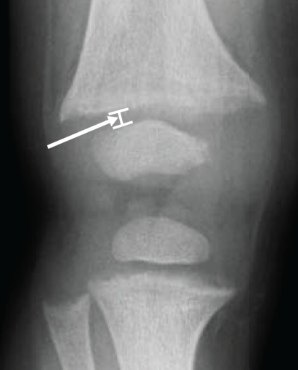

The RSS is a quantitative method that uses radiographs to assess the severity of rickets at the wrists and knees. Originally validated in nutritional rickets, the score is based on the degree of metaphyseal fraying, metaphyseal cupping, and the proportion of the growth plate that is affected. It is a 10-point scale, for which 10 represents the most severe radiographic changes due to rickets and 0 represents the absence of these changes.1

Although the severity and duration of rickets vary considerably between XLH and nutritional rickets, the radiographic features of rickets at the growth plate are similar in the two disorders, which allowed validation of the RSS in XLH. The RSS correlates with serum alkaline phosphatase (ALP) levels, a biochemical marker of rachitic activity, and this scoring system can be used to assess the radiographic response following treatment of nutritional or XLH rickets.

The RSS in XLH has been reported to range from 0 to 4.5; however, despite the smaller RSS range observed in XLH patients, inter- and intra-rater reliability are similar to those reported for nutritional rickets. Patients with XLH who had a baseline RSS ≥1.5 were shown to have more severe hypophosphatemic bone disease, including higher levels of alkaline phosphatase, and greater impairments in clinical outcomes compared with patients who had a baseline RSS <1.5.